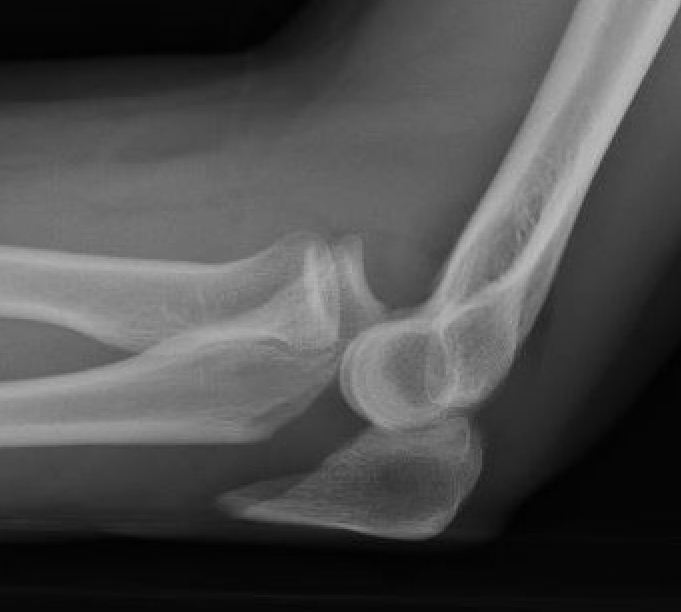

Simple Monteggia fracture - dislocations

Definition

Proximal ulna / olecranon fracture

- posterior radial head dislocation most common in adults

- no fractures

Bado Type II most common in adults with posterior radial head dislocation

Bado type I Bado type II